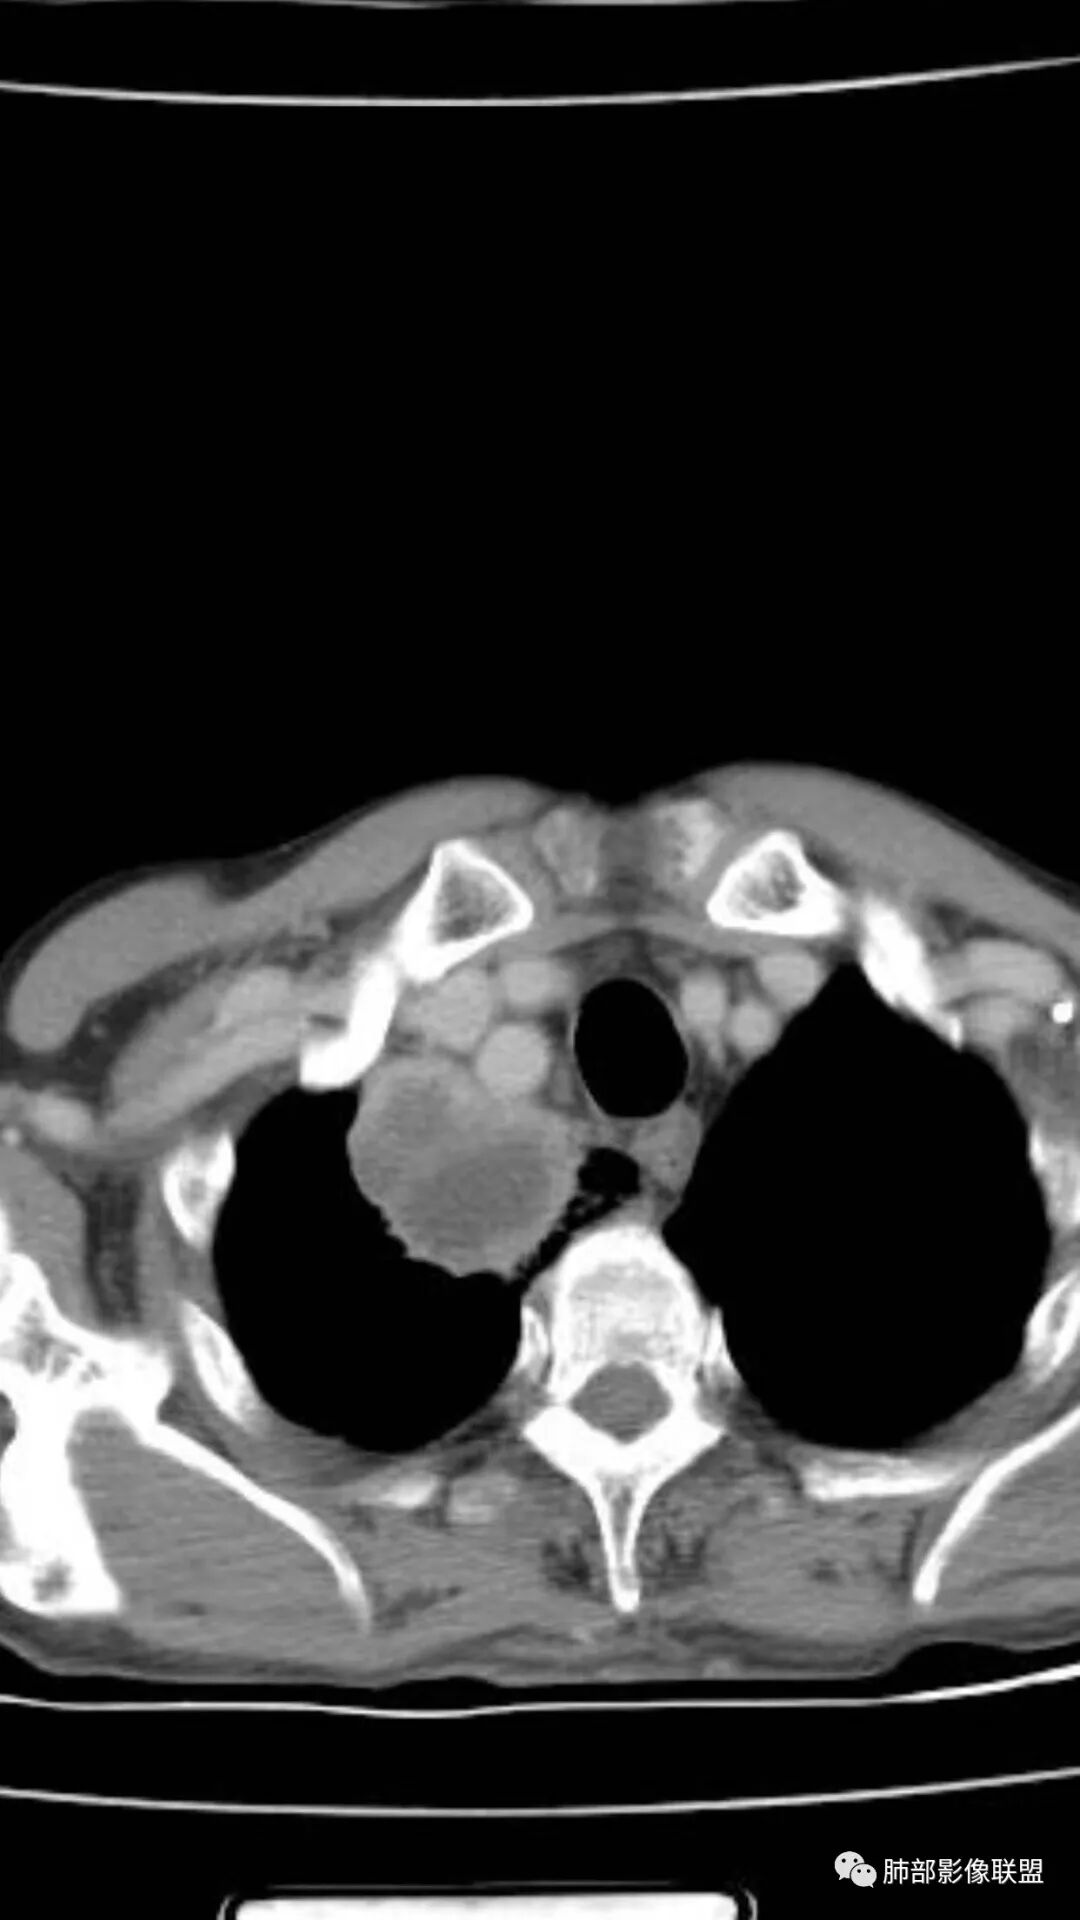

老年人,有高血压、脑梗死、肾结石病史

这次,半月,左胸痛不适,高热:39°C,白细胞、中性粒细胞高

主病灶在右上叶尖段、前段纵隔旁,紧贴胸膜

楔形、边缘膨隆,附近见斑片状、网格状高密度影

患者有高血压、脑梗死、肾结石病史,因左胸痛不适入院,伴高热,血常规示白细胞、中性粒细胞高。胸部CT示右肺上叶肿块影,边缘模糊影,内可见低密度坏死,边界清楚,一月后出现气液平面,周围渗出,治疗2周复查液平及周围炎症吸收,肿块未见明显吸收。

考虑肿瘤?右肺上叶高密度影,边缘模糊,侵及纵隔及胸廓入口,病灶密度不均匀,部分支气管截断,增强后不均匀强化,内可见较大范围坏死,纵隔多发肿大淋巴结不均匀强化。肺上沟瘤不能排除。